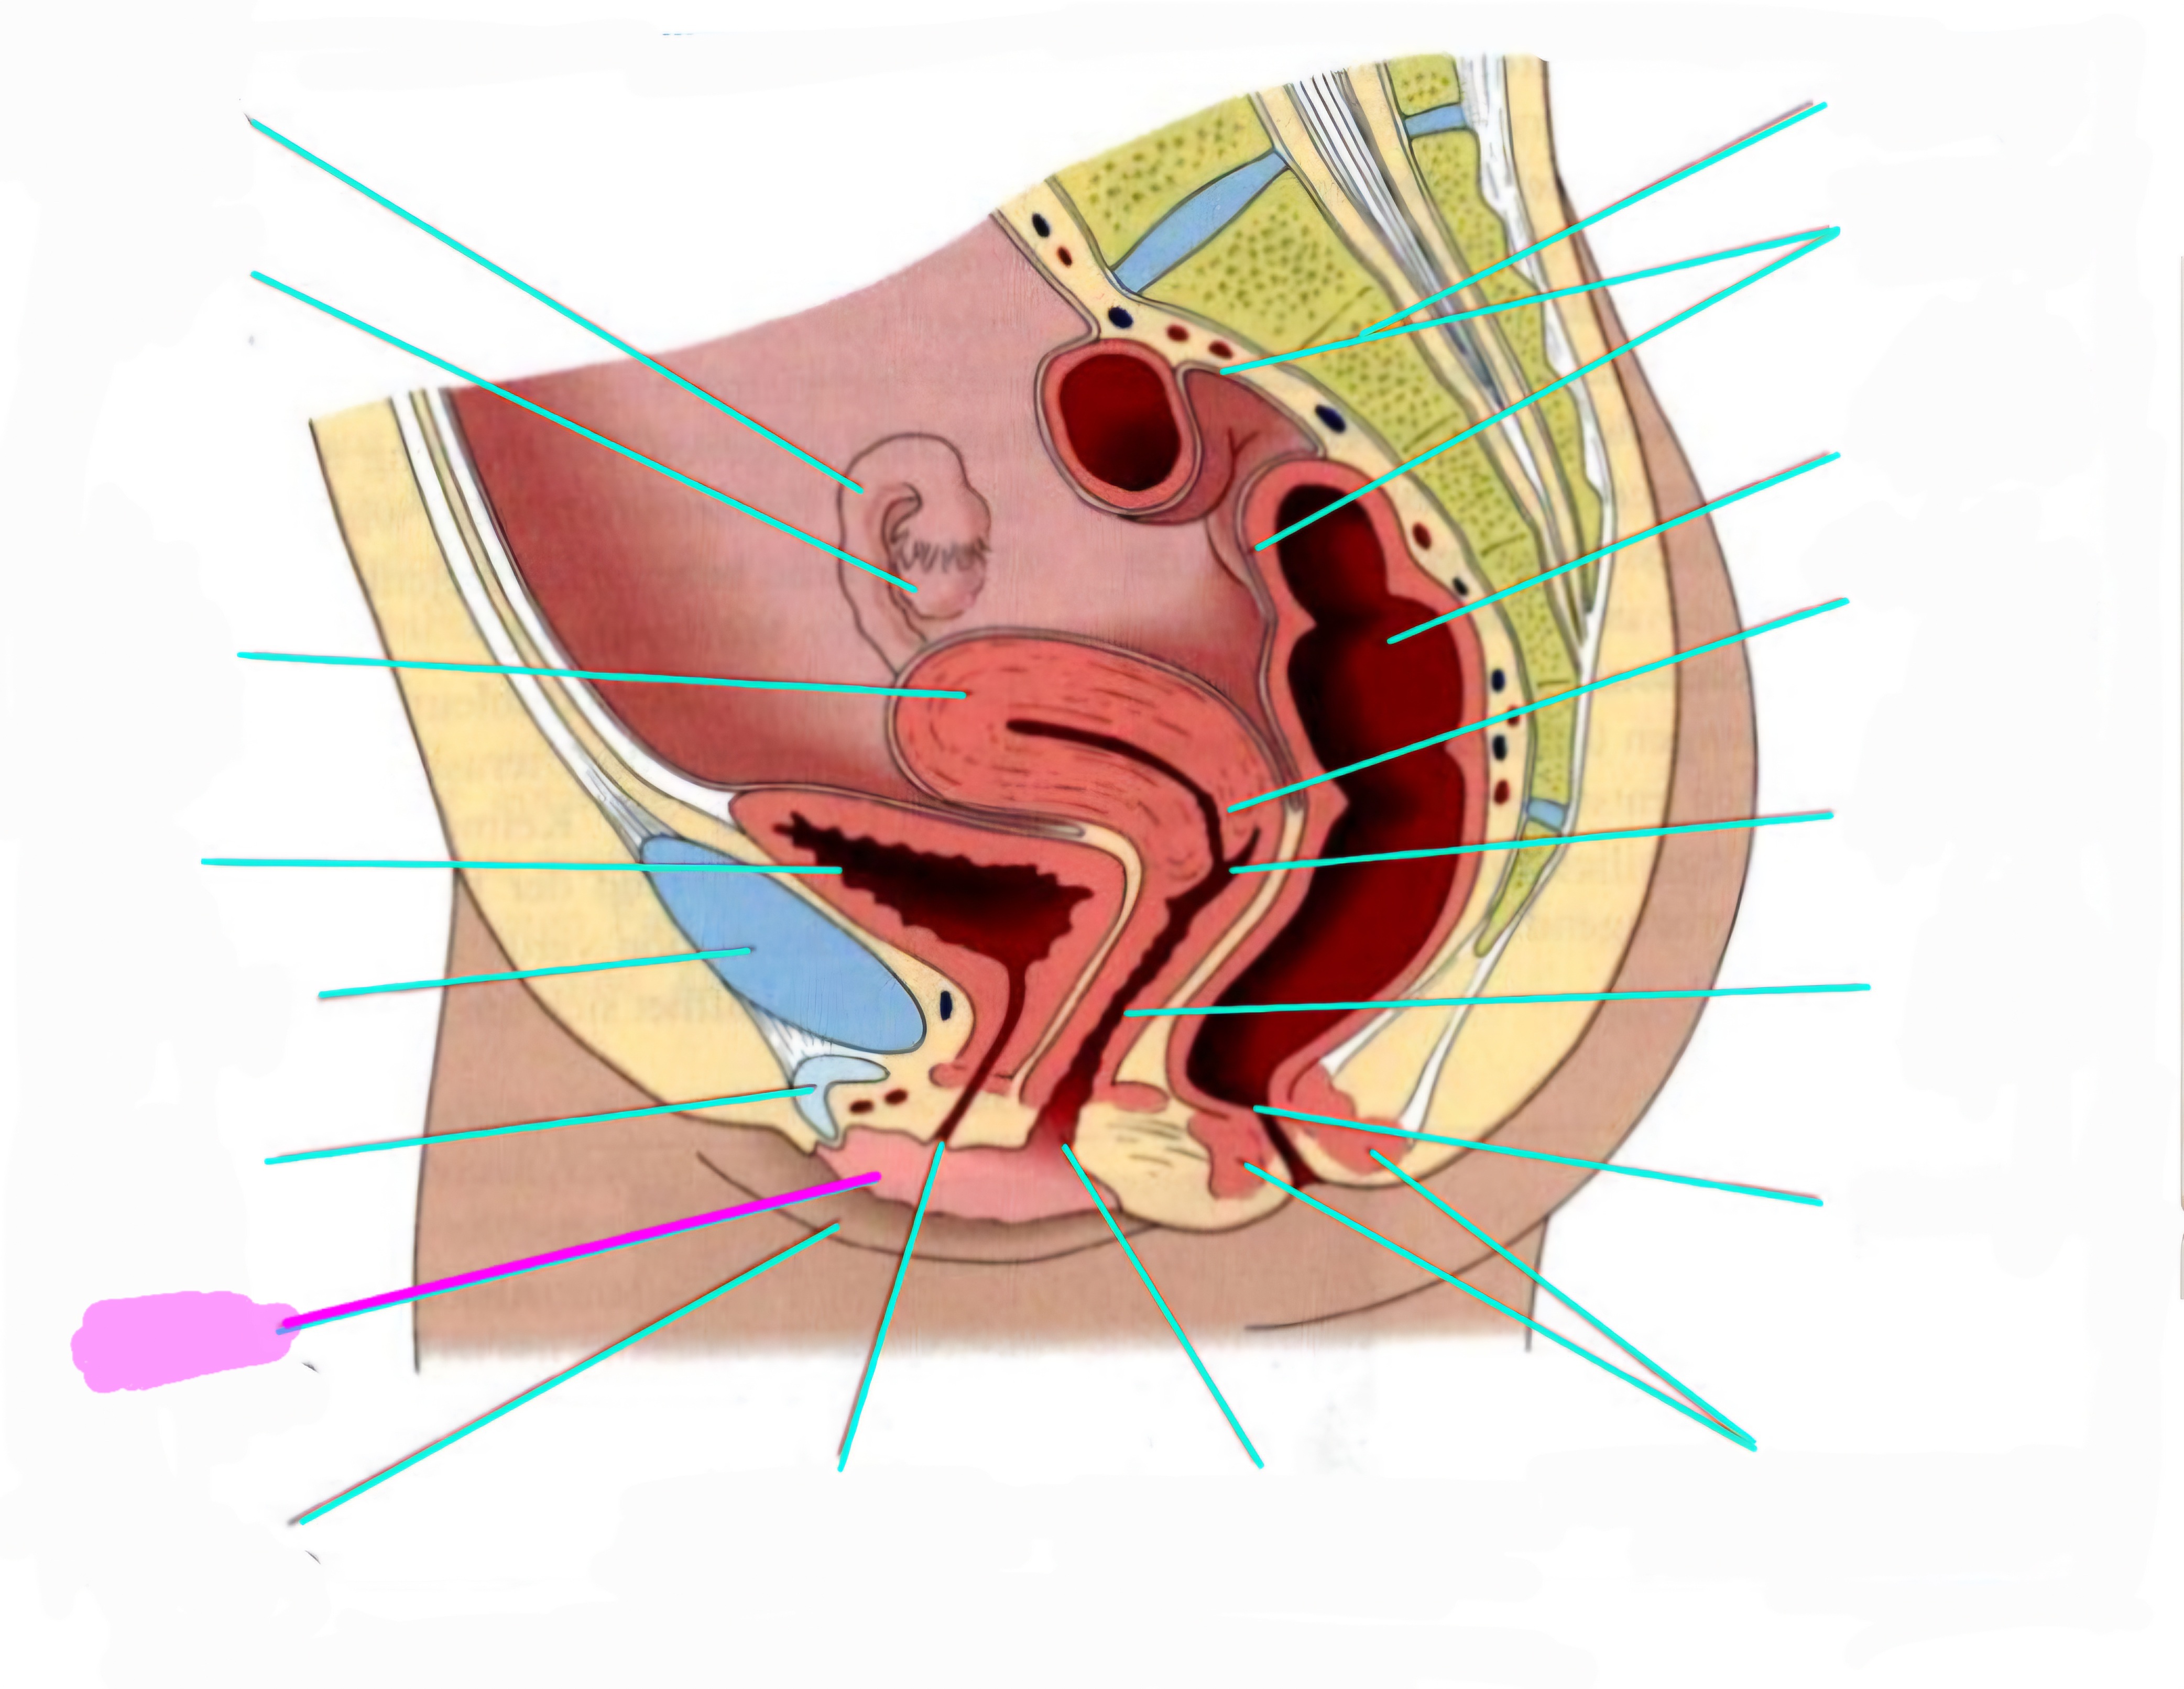

wbl. genital Anatomie

19 Terms

Tubea uterina (Eileiter)

Ovar (Eierstock)

Uterus (Gebärmutter)

Vesica Urinaria (Harnblase)

Symphyse

Klitoris

Labia minor pudendi (kleine schamlippen)

Labia Majoran pudendi (große Schamlippe)

Urethra (Harnröhre)

Introitus vaginae (Scheideneingang)

Sphincter ani externes (äußere Afterschließmuskel)

Anus (After)

Vagina (Scheide)

Portio (äußerer Muttermund)

Rektum (Mastdarm)

Zervix (Gebärmutterhals)

Peritoneum (Bauchfell)

Os sacrum (Kreuzbein)